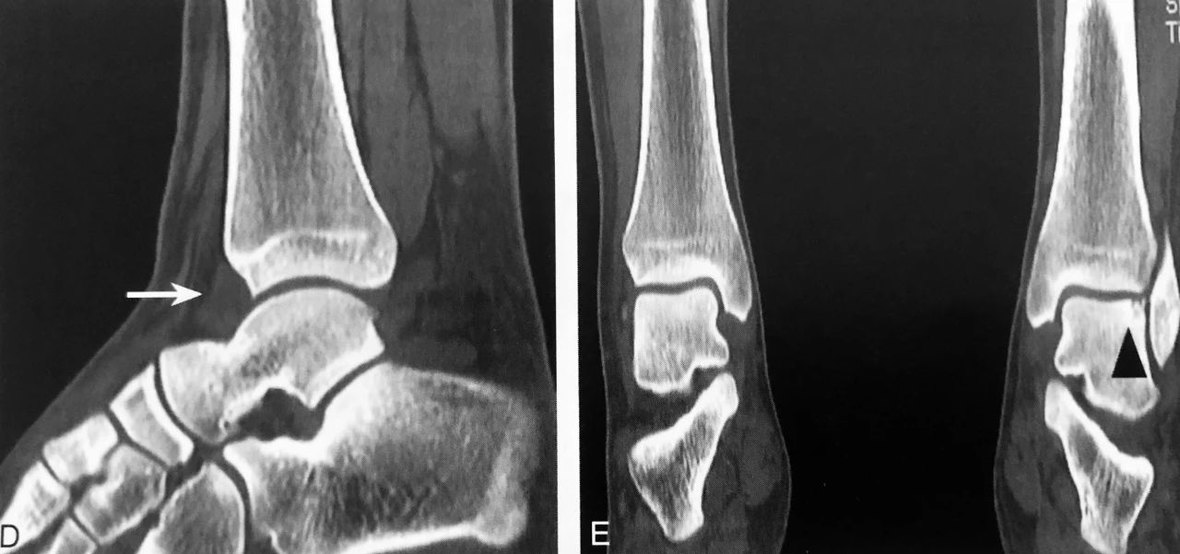

A~E.为同一踝关节外伤患者。A.Ⅹ 线侧位片见“泪滴征”(粗箭头),低密度前脂肪层受压移位变窄(细箭头),提示踝关节积液;B、D分别为踝关节积液MRI、CT表现(长箭头);C、E分别为距骨左份关节面下隐匿性骨折 MRI、CT 表现,MRI 示稍长 T2、长 T1信号,邻近距骨骨皮质连续性可疑中断(三角),CT 进一步明确距骨左份关节面下隐匿性骨折存在(三角)